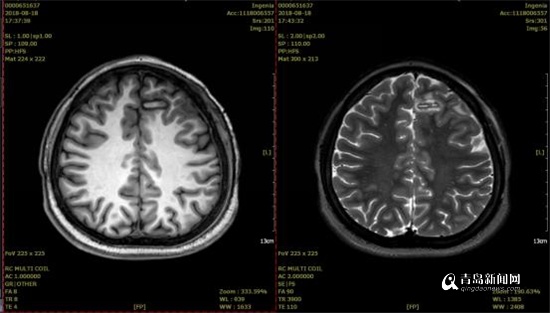

SEEG引導(dǎo)下的射頻熱凝(RF-TC)術(shù)后復(fù)查,顯示毀損范圍滿意。

術(shù)后的腦電圖監(jiān)測結(jié)果顯示,正是術(shù)前高度懷疑的額葉內(nèi)側(cè)面前扣帶回為癲癇起源,同時予以患者小電流刺激相應(yīng)的電極觸點即可誘發(fā)患者平時的慣常發(fā)作,進(jìn)一步證實了之前判斷。SEEG術(shù)后第5天,患者在完全清醒狀態(tài)在接受了SEEG引導(dǎo)下射頻熱凝毀損術(shù),術(shù)中毀損了患者的癲癇病灶,毀損過程中患者沒有一絲疼痛等不適,術(shù)后沒有任何神經(jīng)功能障礙,且術(shù)后效果立竿見影,當(dāng)天停用其中一種抗癲癇藥物后也沒有再次癲癇發(fā)作,拔出顱內(nèi)深部電極后復(fù)查顱腦MRI見毀損范圍與之前判斷的癲癇病灶重疊良好,患者滿意出院。